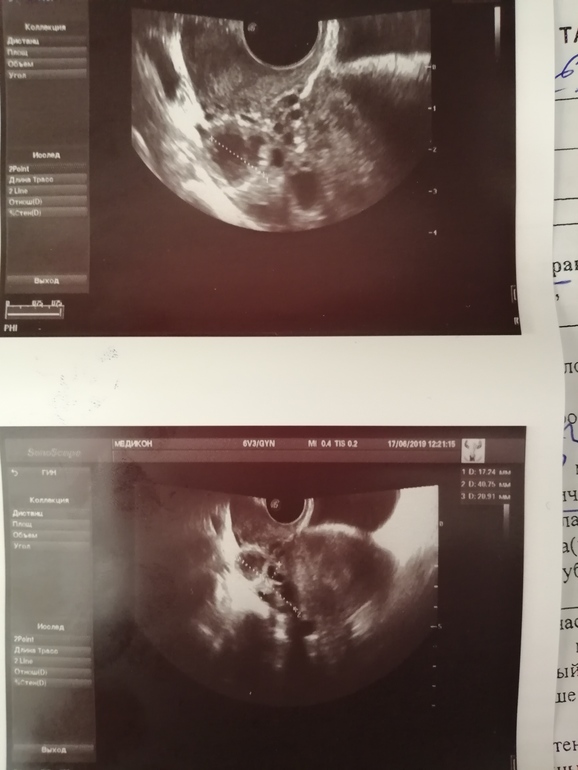

Всем добрый день, 13.06 делала укол ХГЧ 5000, сегодня пошла на узи проверить лопнул ли фолликул. Узиста у кого я обычно делаю без врача к сожалению не было, записали к другому. Узист совсем ничего не обьяснил, сказал есть желтое тело минструальное сморщенное какое то. Как и почему не могу понять и в какую сторону копать. Так и не смог мне обьяснить лопнул или чтл с ДФ, фолликул был около 19мм за несколько часов до укола (на стимуляции вырос). Помогите понять что узист написал, что это за желтое тело или дайте наводку в какую сторону копать..

Сходила посмешила своего репродуктолога, вчерашним походом на узи... Повторили узи, в итоге: имеется отличное ЖТ и не много жидкости в позадиматочном пространстве, никаких намеков на кист в обоих яичниках нет...

ну, согласна с предыдущими, что жт только при овуляции, но в описании узи написано, что нет свободной жидкости, а она при о должна быть. и чесно говоря, надо бы к еще одному сходить узисту

Бывает, почитайте про лютеинизацию фолликула, когда ДФ не лопаясь "перерождается" в ЖТ, О нет в этом случае, а ЖТ есть.